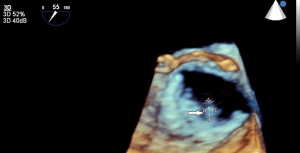

Both transthoracic echocardiography (TTE) and transoesophageal echocardiography (TEE) are the main imaging modalities for diagnosis of IE The European Society of Cardiology (ESC) classify echocardiography as 1B recommendation with echocardiographic results an important Duke criterion (2). Diagnosis based on echocardiographic images has high sensitivity and specificity to detect vegetations, a distinctive sign of IE, particularly if it measures >5 mm (Table 1) and for valve detachment (3). It is however less accurate when it comes to detecting abscesses, aneurysms, pseudoaneurysms, and fistulas. Echocardiography allows the rapid detection of vegetations (Figures 1,2), by measuring the major and minor axes of these, in addition to allowing differentiation from other intracardiac masses, informing the operator on location, mobility (fixed, mobile, oscillating) (Figure 3), echogenicity and potential complications such as the presence of leaks, fistulas, and dehiscences (2,4).

In a study of suspected right-sided endocarditis, TTE performed as well as TEE in the detection of vegetations (22). RT3D TEE also has a role in patients with tricuspid valve IE as it allows enhanced visualization of the tricuspid valve apparatus, vegetations, and surrounding structures compared to 2D TEE (23). In patients with a tricuspid ring or tricuspid valve prosthesis and/or electrophysiological devices, RT3D echocardiography can detect vegetations and their exact origins, permitting real-time therapeutic interventions or device extraction (Figure 5).